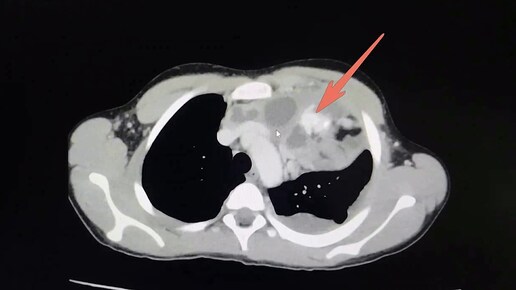

02:311,0×00:00/02:31Аномальное отхождение правой коронарной артерии от ствола лёгочной артерии4 месяца назад